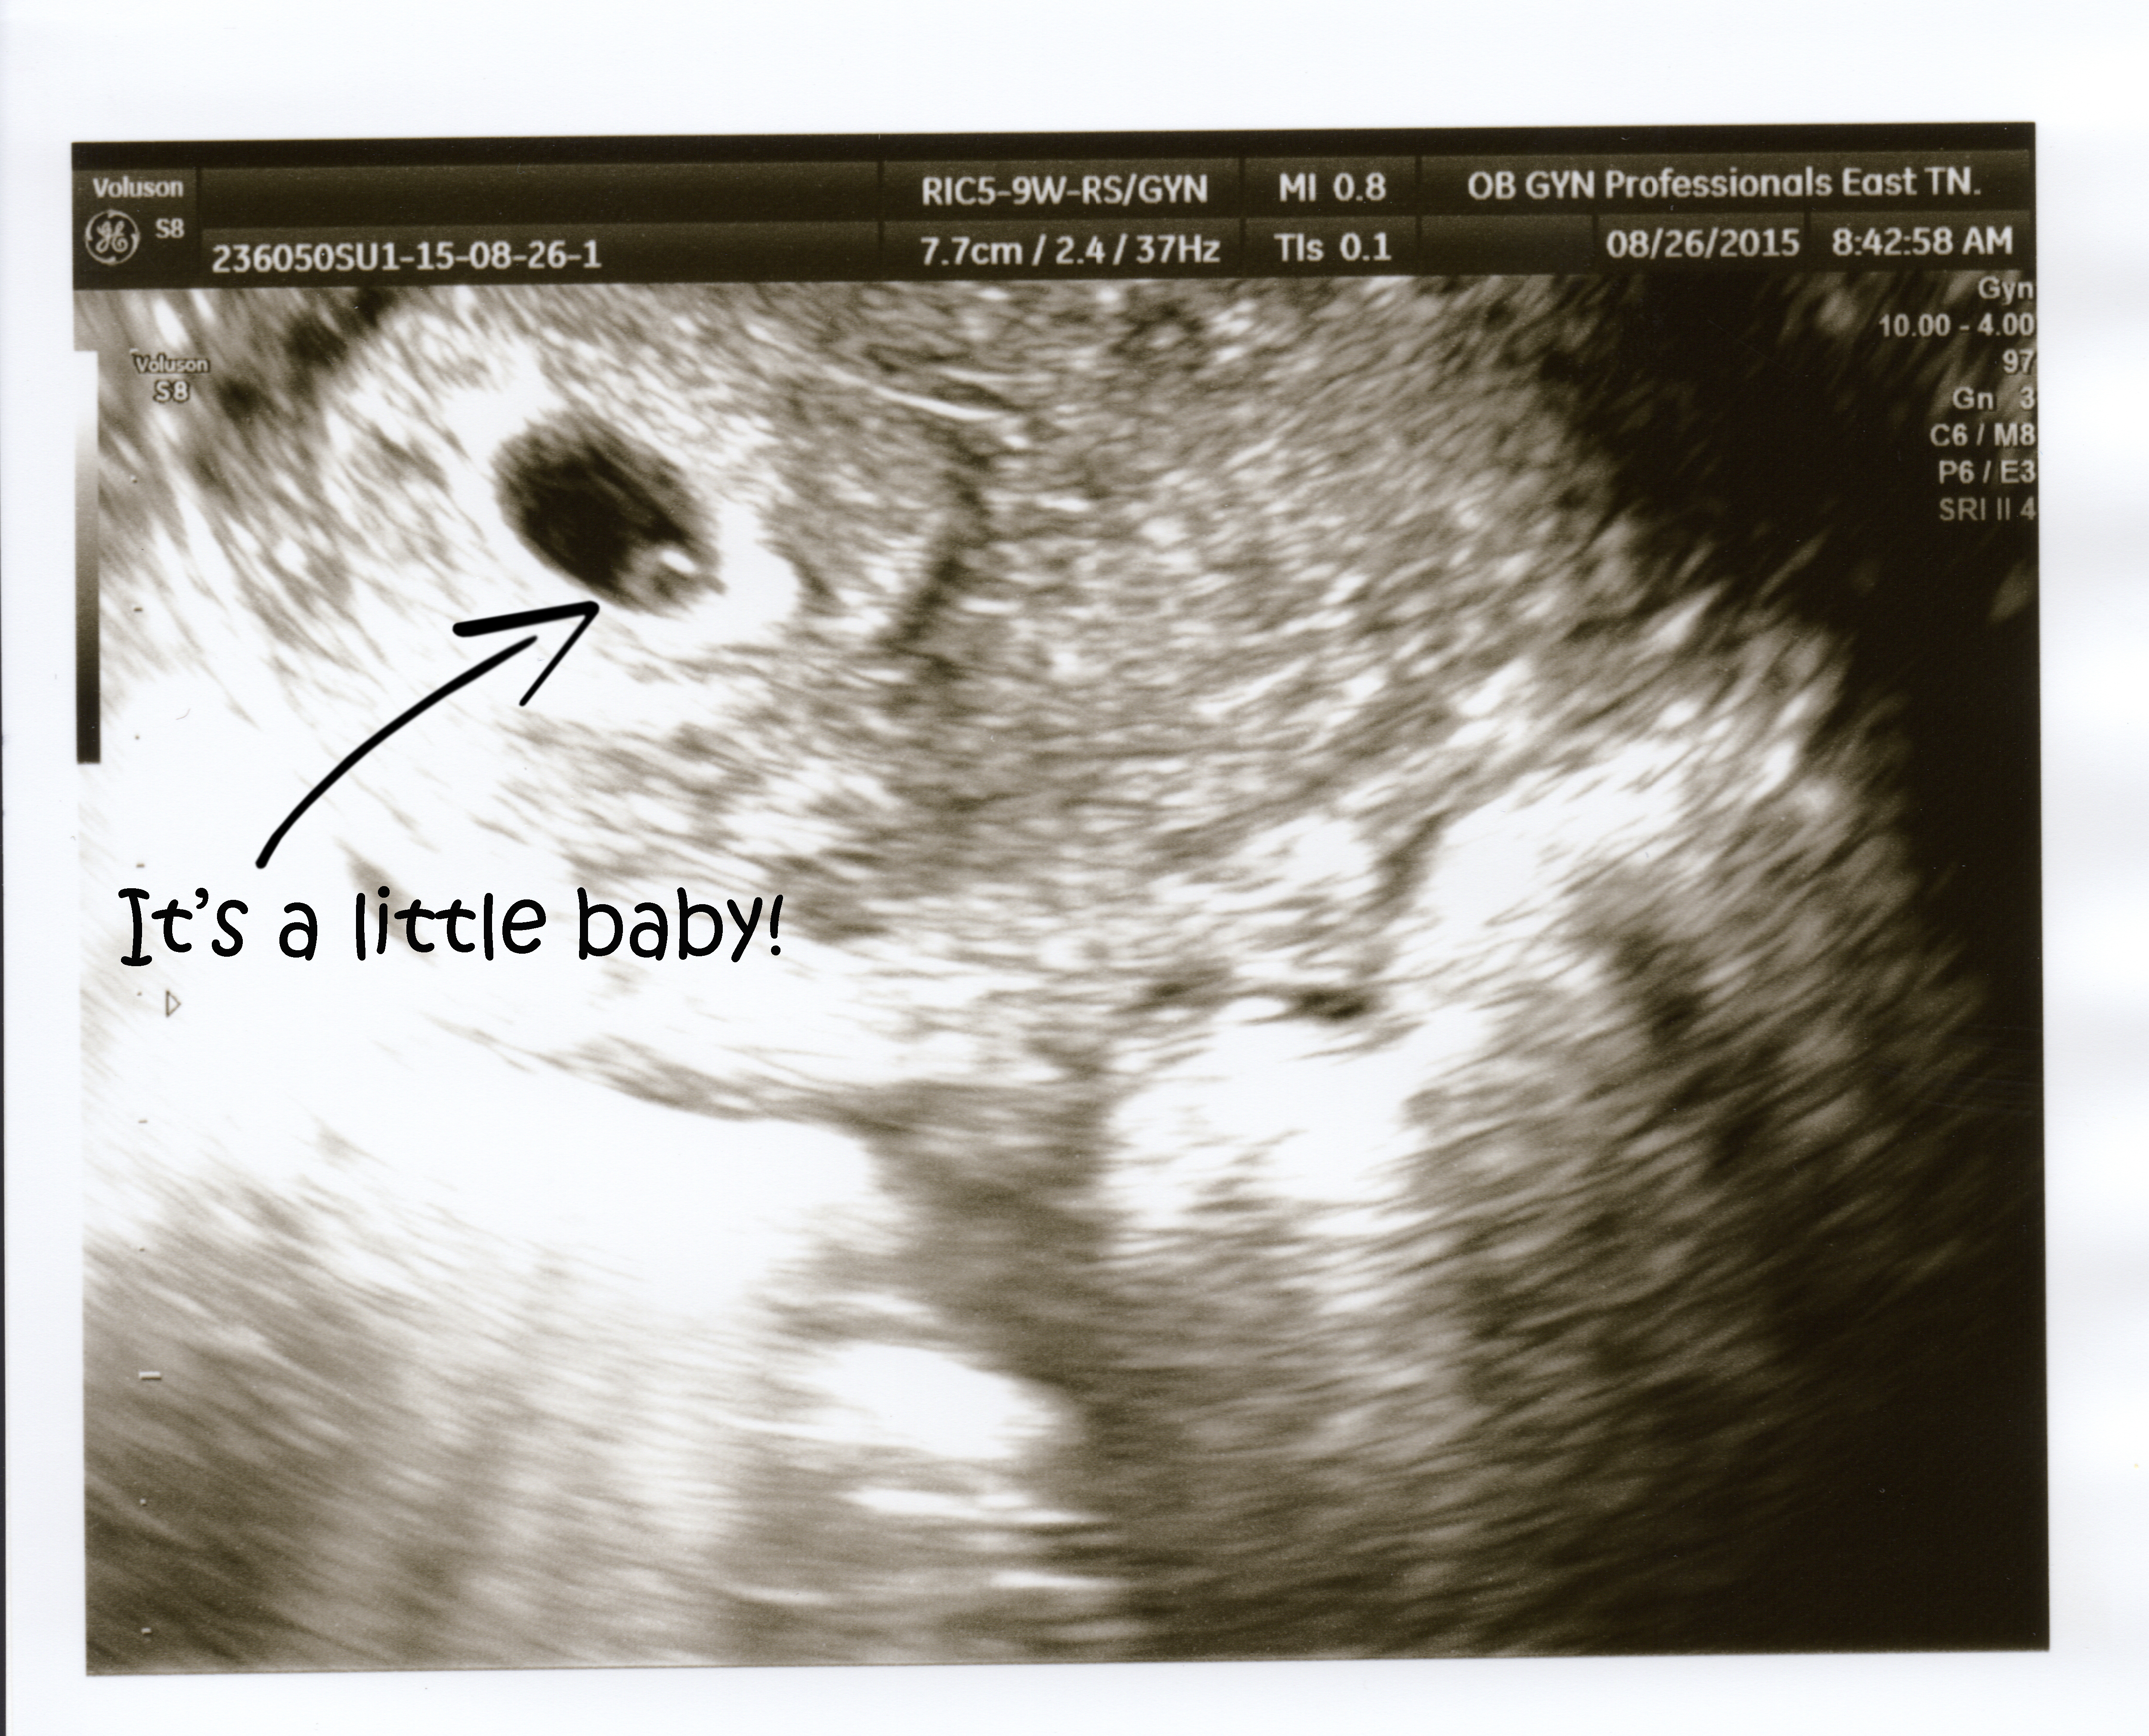

It's been a while since our last update, but we'd like to announce some exciting news! We're expecting our first baby!